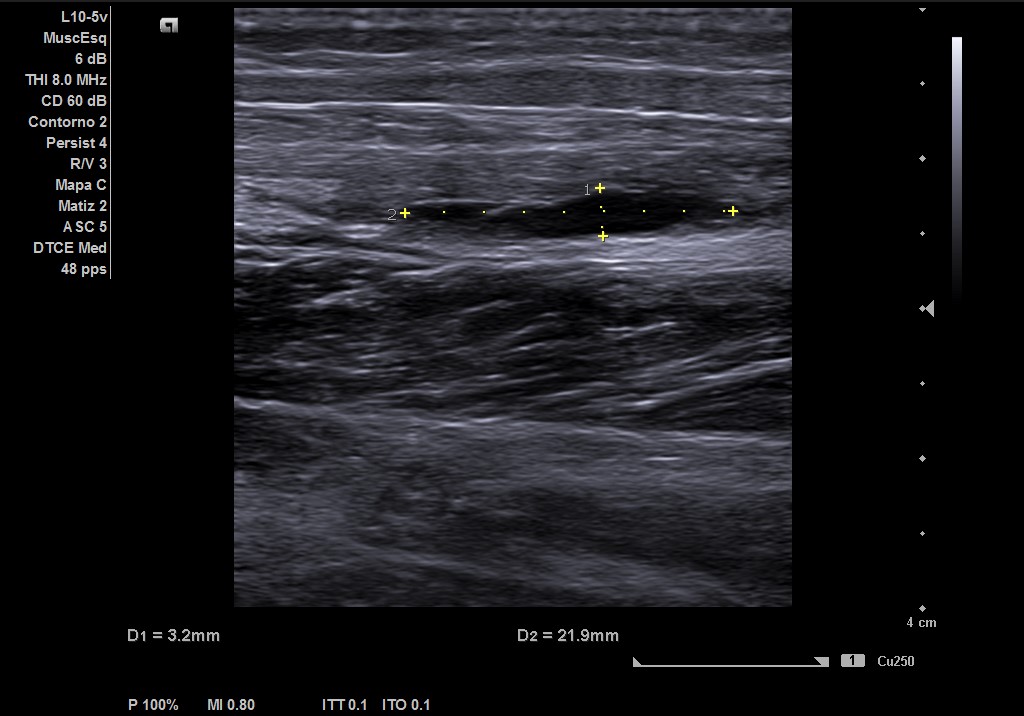

Objetivamos dolor a punta de dedo en zona del gemelo izquierdo con contractura asociada, no otras alteraciones en el resto de explotación de MII. Ante la sospecha de rotura fibrilar, realizamos ecografía.

Descripción de los hallazgos ecográficos y las imágenes más relevantes para la resolución del caso

Ecografía musculoesqueletica: se objetiva signos de rotura de inserción gemeral interno-soleo de 21 x 32 mm y línea de líquido en zona superior intergastronemios de 1 mm de grosor. Doppler negativo.